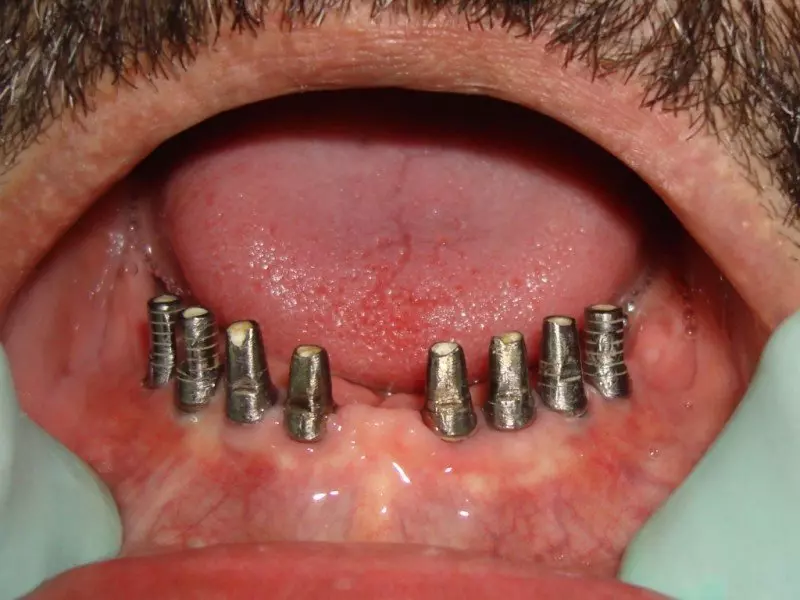

These 3 dimentional raw images run in a deisigning software and a surgical templates prepared with the anticipatory ideal dental implant positions with a cad cam technology. Specialized computer software enables implant surgeons to assess all of the critical areas of the maxillary and mandibular bone structures. The precision imaging helps dentists to not only determine the best possible implant sites but also permit the assessment of need for bone augmentation (grafting) that will optimize predictability ratios.

The entire procedure of assessment, treatment planning, selection of implant systems and final prosthesis  planned “virtually” before treatment begins. Patients benefit from being able to visualize, fully, current state of need and final outcome possibilities, based on their choice of restoration components (types of crowns, abutments, shape, color shading, size, etc).

These technology also can be used for designing the CAD CAM prosthesis made on dental implants.